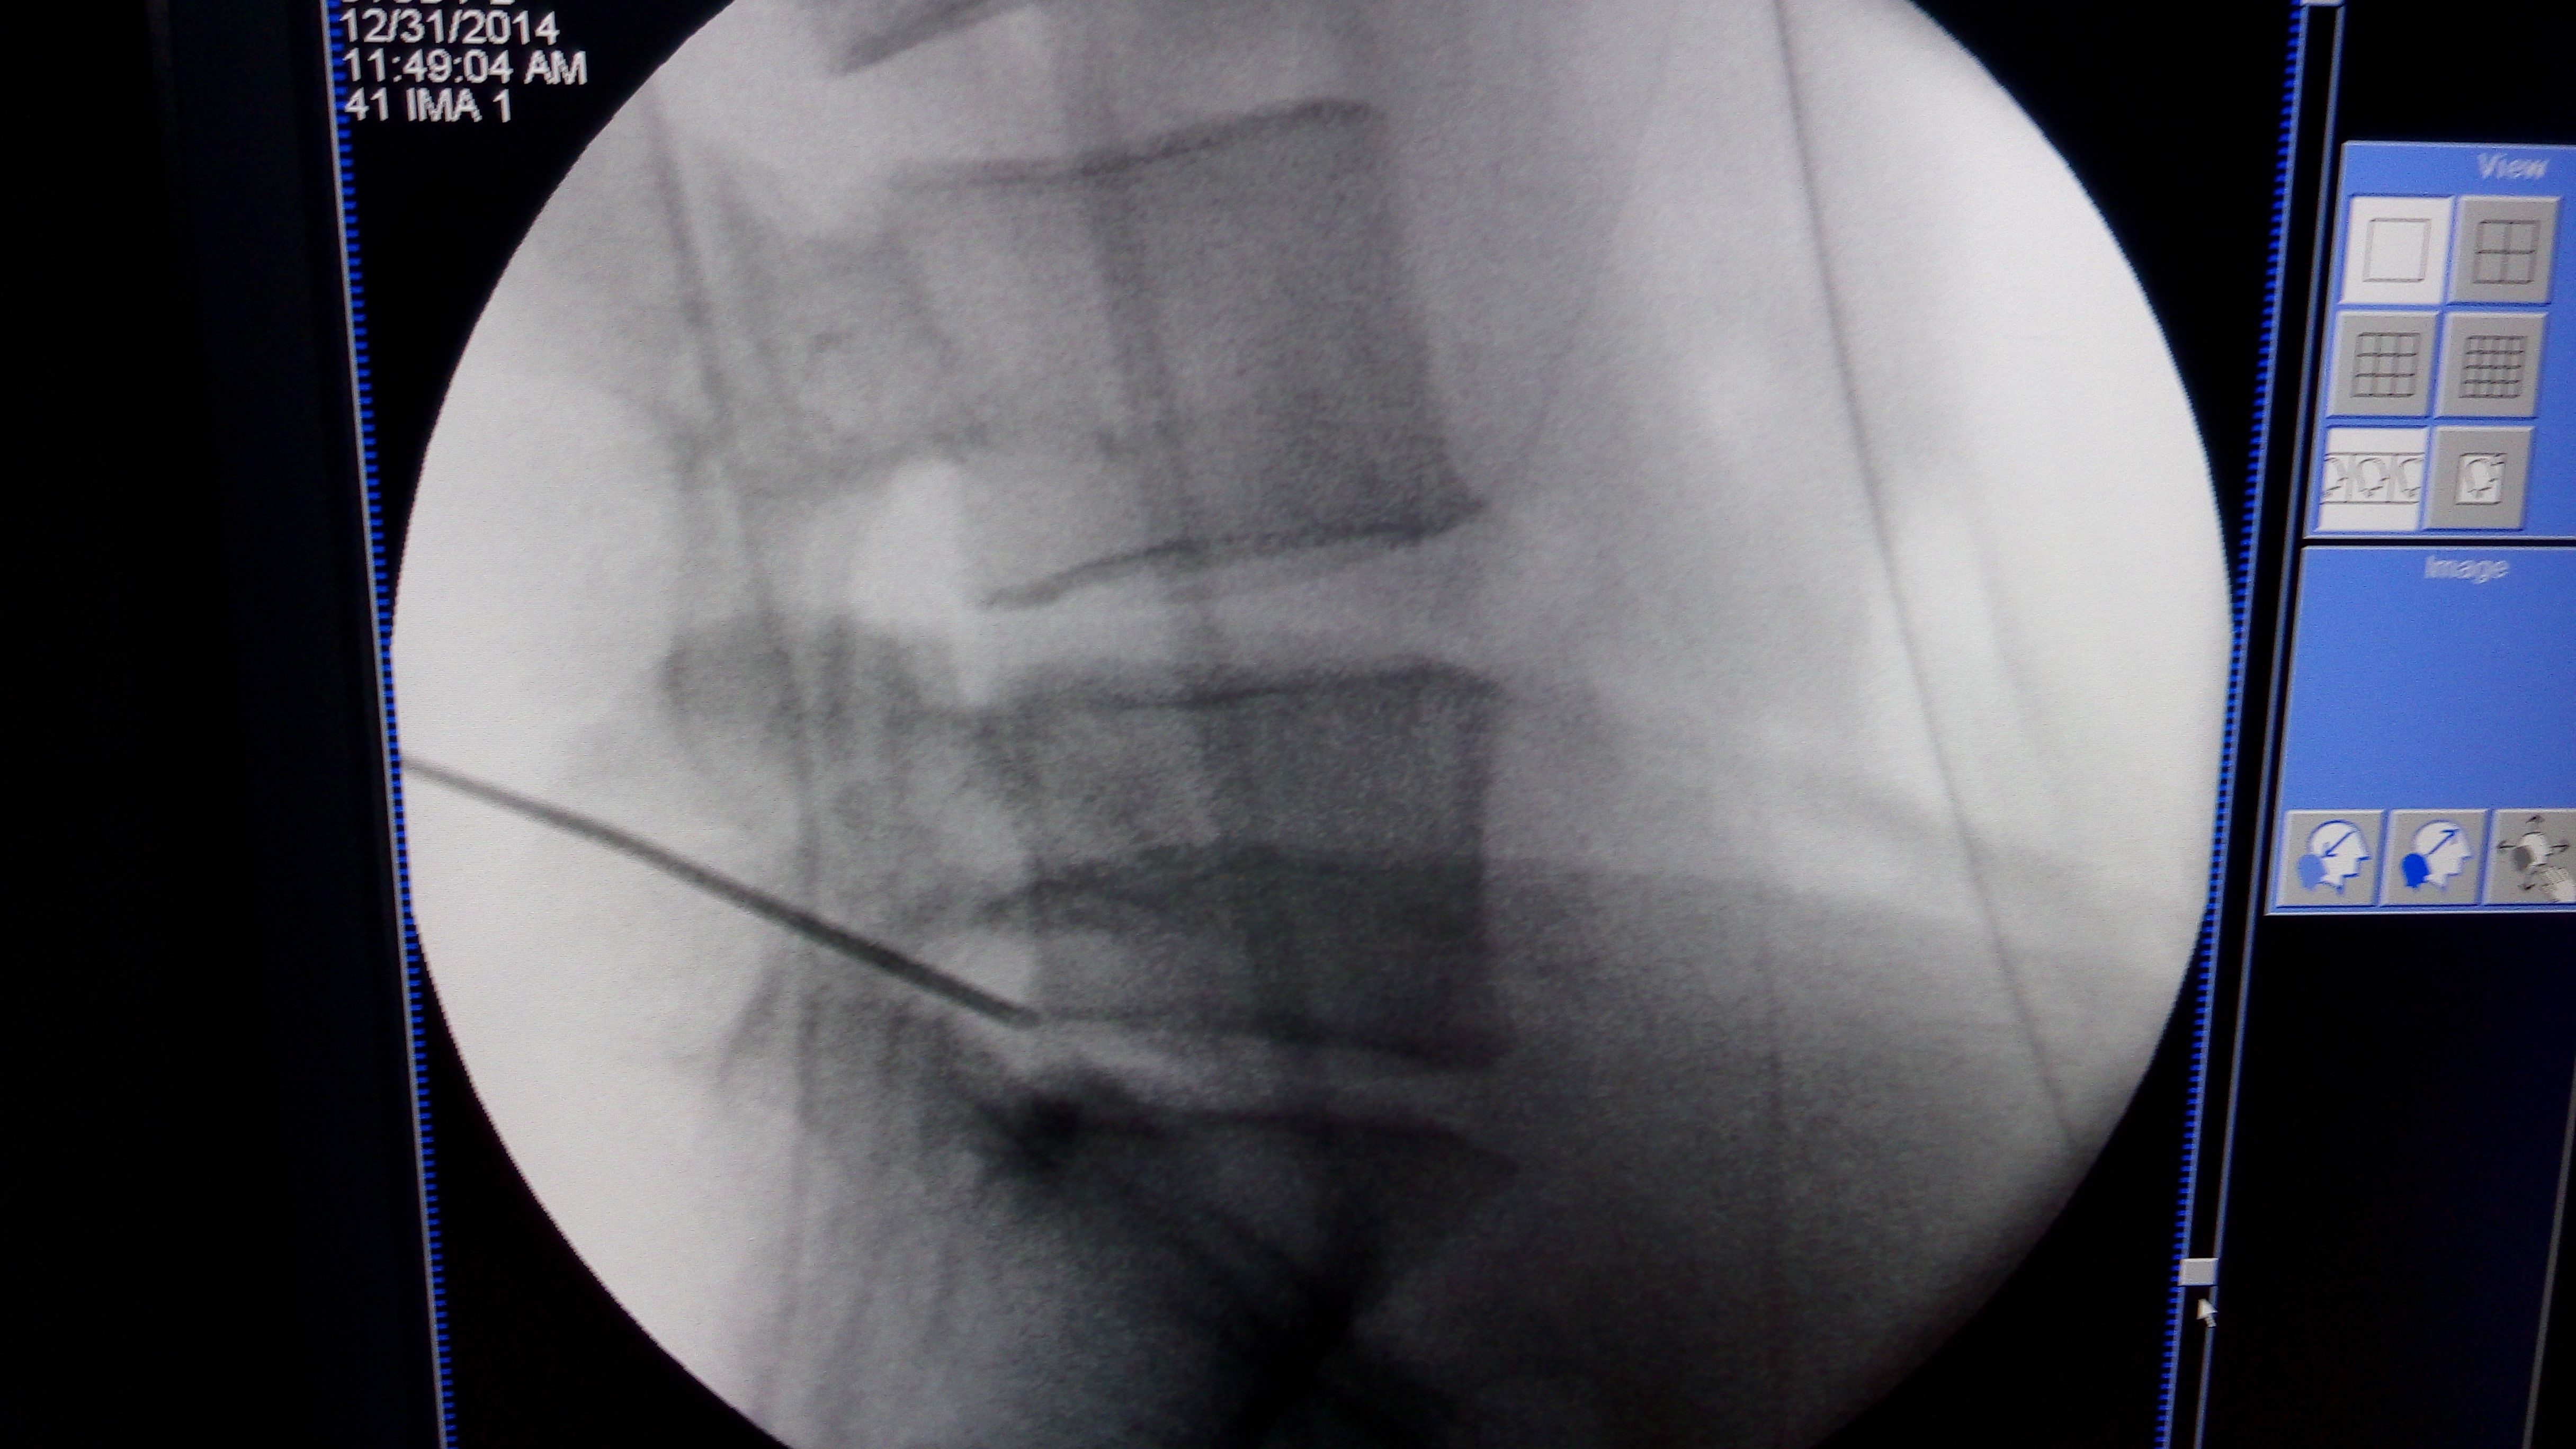

在造影前,应将有关脊髓造影的方法详细地向患者说明。造影前进行水化疗法可减少造影后的反应。很少需要强作用的镇静剂。合适的设备包括带有点片装置、图像增强、可倾斜检查台及电视监视器的荧光屏透视系统,这些装置非常有用。

病人俯卧于透视台上,可在腹部垫一枕头,背部按手术要求准备。根据病变节段选择进针点。由于可能损伤圆锥,选择L2~3以上的椎间隙作为进针点有一定危险。

穿刺区作局部麻醉。选用利于穿刺的小号针,如应用Whitacre型穿针,因其针头钝,不易穿透组织,可先用一19号针穿过皮肤,皮下组织和筋膜以形成一通道。选后正中线进针能减少刺激外侧的神经根和注入硬膜外的可能性。进针时针尖斜面应与身体纵轴平行。将病人置于头高脚低位可增加椎管内压力,减小硬膜外间隙,使穿刺更易于进入蛛网膜下腔。

在透视下注入少量造影剂可协助确认针尖在蛛网膜下腔,如怀疑注射的造影剂一部分在硬膜下腔,另有一部分在蛛网膜下腔,那么应改变进针深度,有时需要拍摄侧位X线片以确保进针达合适的深度。如脑脊液流出正常,即可缓慢注入造影剂。

使造影剂流向尾端,以便观察腰神经根和远侧硬膜囊。在前后位、斜位及侧位点片。完整的检查应包括高达T7平面的胸椎,因为胸椎平面的病变也可出现类似腰椎间盘病变的表现。在造影剂向头端流动的过程中,再进一步补充点片。